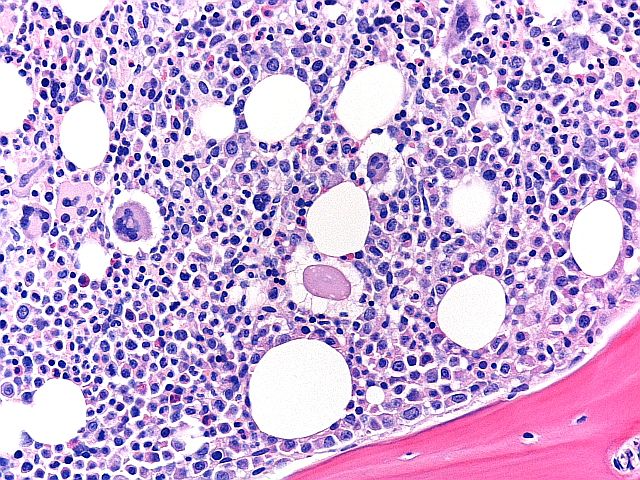

Hæmatoxylin og eosin - Nyreskema

Set ved x4 er dette et eksempel på et hæmatoxylin- og eosin-farvet præparat. Ud over folderne, krøllerne og løftningen blev der også fratrukket point for hæmatoxylin-baggrundsfarvning og svag eosinintensitet. Dette præparat fik en score på 7/10.